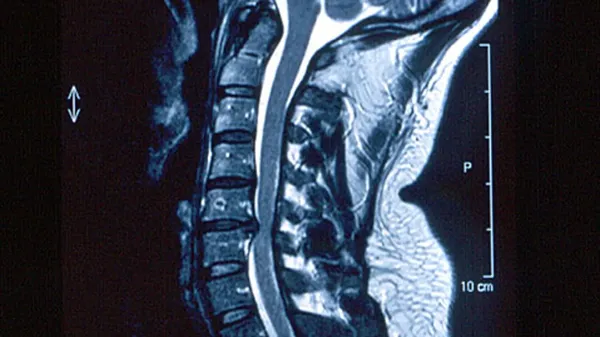

LA TERAPIA . L’ozonoterapia è un trattamento basato sulle capacità antinfiammatorie, antibatteriche, antivirali e antalgiche dell’ozono.